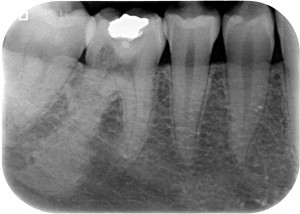

Riassorbimento esterno - Cavità esplorativa Dutto

Con un cucchiaino ho prelevato un po’ di quel misterioso tessuto, probabilmente impiantato da qualche alieno nel sonno, pensavo io, alla povera malcapitata e dopo aver fatto questo prelievo delicatissimo ho continuato a scavare fin dove potevo cercando un tessuto sano ma facendo estrema fatica a capire se a un certo punto mi trovavo sul nervo o se era ancora il dente a sanguinare.

Riassorbimento esterno - impianto di tessuto alieno

Non volendo arrivare alla devitalizzazione, perché non avrei saputo come portarla a termine in mancanza della radice distale, ho fatto un’otturazione in composito.